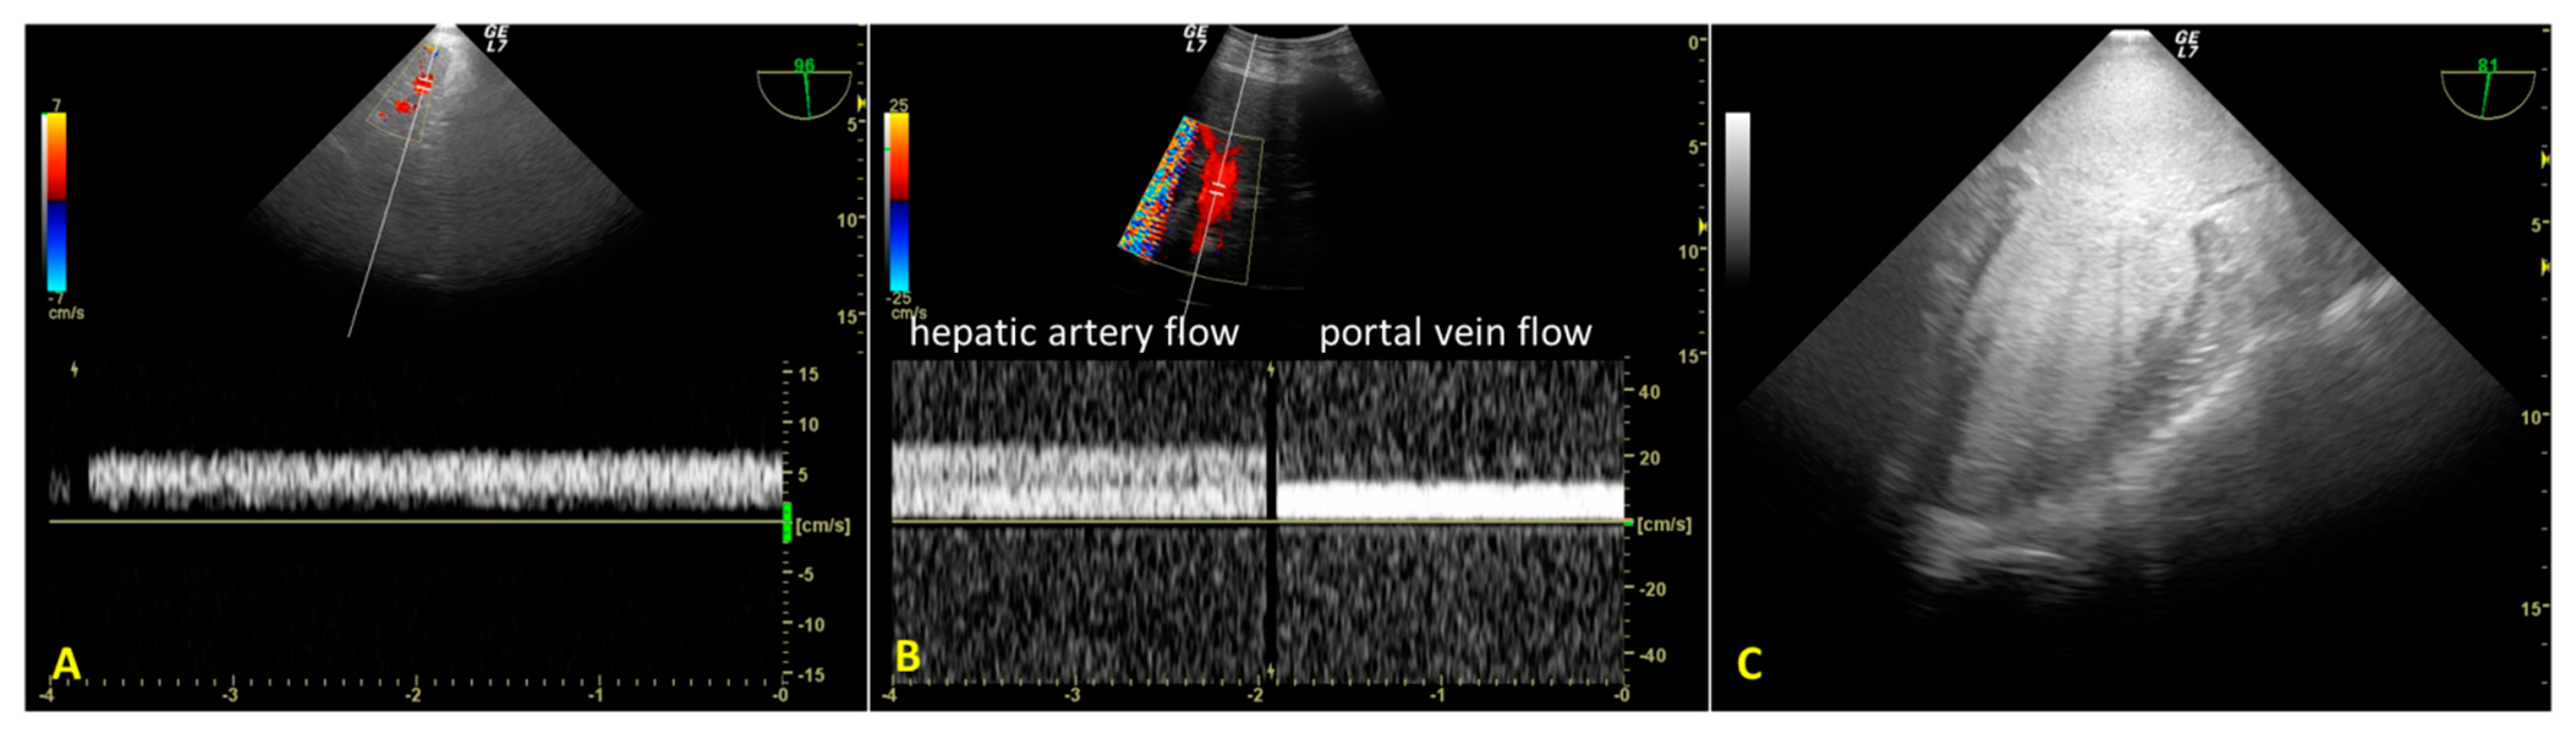

We used an introducer needle to insert a Super Stiff guidewire into the right femoral vein until the right atrium. Correct positioning of the guidewire was verified in real time using the TEE mid-esophageal bicaval view (Figure 1A). Next, we inserted a second guidewire through the right femoral artery sheath and introduced it up to the thoracic aorta. After visualizing the wire’s tip within the thoracic aorta using the mid-esophageal descending aorta short-axis view, we partially withdrew the guidewire so that its tip stopped below the diaphragm. These two guides allowed the introduction of venous and arterial A-NRP cannulae post-mortem.

Finally, we introduced a third guidewire through the left femoral artery sheath to allow proper stent placement for aortic occlusion. TEE use guided and monitored correct positioning using the mid-esophageal descending aorta long-axis view (Figure 1B,C). Using fluoroscopy, we double-checked the proper positioning of the guides and aortic occlusion catheter (AOC).

Figure 1. (A). Mid-esophageal bicaval view. The guidewire (*) was inserted through the inferior vena cava into the right atrium. (B). Mid-esophageal descending aorta long-axis view. The aortic occlusion catheter is visualized in the thoracic aorta; the deflated balloon is located just above the diaphragm. (C). Mid-esophageal descending aorta long-axis view during A-NRP. The position of the AB (inflated) remained unchanged above the diaphragm. IVC—inferior vena cava; RA—right atrium; SVC—superior vena cava; * guidewire; Ao—aorta; AOC—aortic occlusion catheter; LA—lung atelectasis; Dia – diaphragm; DB—desufflated balloon; IB—inflated balloon.